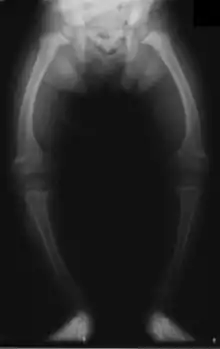

Le genu varum est une déformation (un trouble orthostatique) du membre inférieur, qui siège dans l'articulation du genou, mise en évidence après avoir demandé au sujet debout de coller ses chevilles l'une à l'autre (les malléoles médiales se touchent) et en observant l'absence de contact entre les deux genoux.

On dit que « les jambes sont arquées ». Il est possible d'objectiver le genu varum par la mesure de la distance entre les faces médiales (les faces internes) des genoux.

Est considéré comme anormal un genu varum asymétrique ou unilatéral, ainsi qu'un genu varum continuant de s'aggraver après l'âge de 2 ans, et une distance intercondylienne supérieure à 3 cm chez le préadolescent[1].